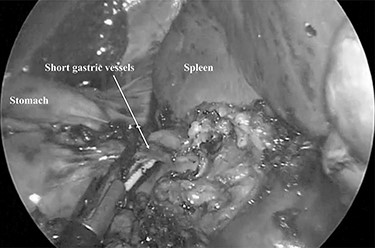

A 79-year-old female patient who had been diagnosed with chronic ITP in September 2014 presented at our hospital. She had received a combined therapy comprising prednisolone and thrombopoietin receptor agonist; however, her platelet count ranged from 0.5 to 59.9 × 104/ul and could not be controlled with oral therapy. Furthermore, she had comorbidities including hypertension, dyslipidemia and diabetes mellitus induced by pre-dnisolone, and a past history of cholecystectomy with an upper abdominal incision. She underwent NS in October 2015, and there were dense adhesions around the spleen supposing to the previous upper abdominal surgery (Fig. 1). The duration of surgery was 163 min and an intra-operative blood loss was 10 ml. Post-operative CT showed a low volume of ascites, which did not require further treatment. She was discharged on the post-operative day 9 with an extremely high her platelet count (135.2 × 104/ul). The weight of the resected specimen was 135 g. Her post-operative platelet count settled at around 45 × 104/ul during 54 months after surgery.

Dense adhesions around the spleen were divided under 3-mm needlescope.

Minimally invasive abdominal surgery performed with needlescopic instruments leads to minimal surgical trauma to the abdominal wall, improved cosmetic result, reduced postoperative pain, lower incidence of wound complication, no risk of port site hernia and earlier recovery. Initially, we used of 2-mm needlescopic instruments for laparoscopic splenectomy (LS); however, the shaft easily bent when manipulating the organs, and there is a high frequency of a butting between the 2-mm needlescope and another forceps due to close proximity to the organs, with a narrow angle of surgical view [2]. Therefore, we utilized 3-mm instruments to overcome the restriction of surgical optics and maneuverability and provide better convenience for the surgeons. However, the risk of tissue damage by the pointed ends of fine graspers or splenosis [3] due to the capsular disruption of the spleen still remains. The dense intra-abdominal adhesions due to previous upper abdominal surgery as seen as Fig. 1 of Case 2 need careful dissection to prevent splenosis. This leads to a longer duration of surgery.